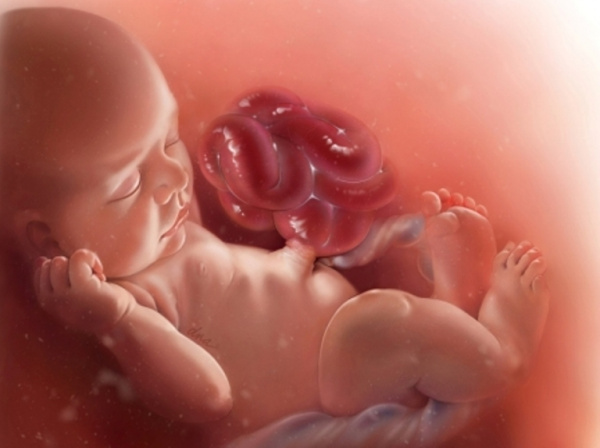

В течение первой трети внутриутробной жизни кишечник лишен твердого содержимого. Начиная с четвертого месяца развития в его полости появляется содержимое, количество которого все более увеличивается. Это содержимое, названное меконием, по своему происхождению гетерогенно и состоит из смеси отпавших эпителиальных клеток, слизи и желчи, т. е. из веществ самого развивающегося пищеварительного тракта, а также из веществ, которые поступают в кишечный тракт вторично — из окружающей амниотической жидкости.

Материал, который заглатывается эмбрионом, включает в себя эпителиальные клетки, волосы зародышевого пушка (lanugo) и некоторое количество сального секрета (vernix caseos), покрывающего кожу зародыша. Вплоть до рождения содержимое кишечника стерильно, но вскоре после того как младенец начинает питаться через рот, в кишечнике появляется бактериальная флора.

Зеленоватый цвет мекония, обусловленный тем, что содержимое кишечника в течение длительного времени испытывает действие желчи, резко отличается от характерного желтого цвета экскрементов, который появляется после принятия пищи. На четвертый день после рождения все следы мекониальной окраски содержимого кишечника исчезают. Этот факт иногда может иметь значение для установления времени рождения.